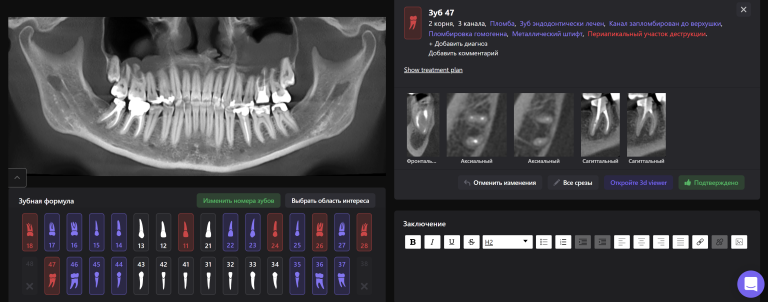

Для принятия клинического решения врач проанализировал данные осмотра и рентгенологического отчета Diagnocat. В отчете содержится оценка ранее проведенного лечения и данные о наличие признаков периапикальных изменений

Обратите внимание на высокий процент вероятности, который предлагает Diagnocat. Принято решение о сохранении зубов и проведении повторного эндодонтического лечения

«Эндодонтический отчет» Diagnocat помогает зафиксировать изначальный объем периапикального очага и изучить анатомию и морфологию корневых каналов до начала лечения